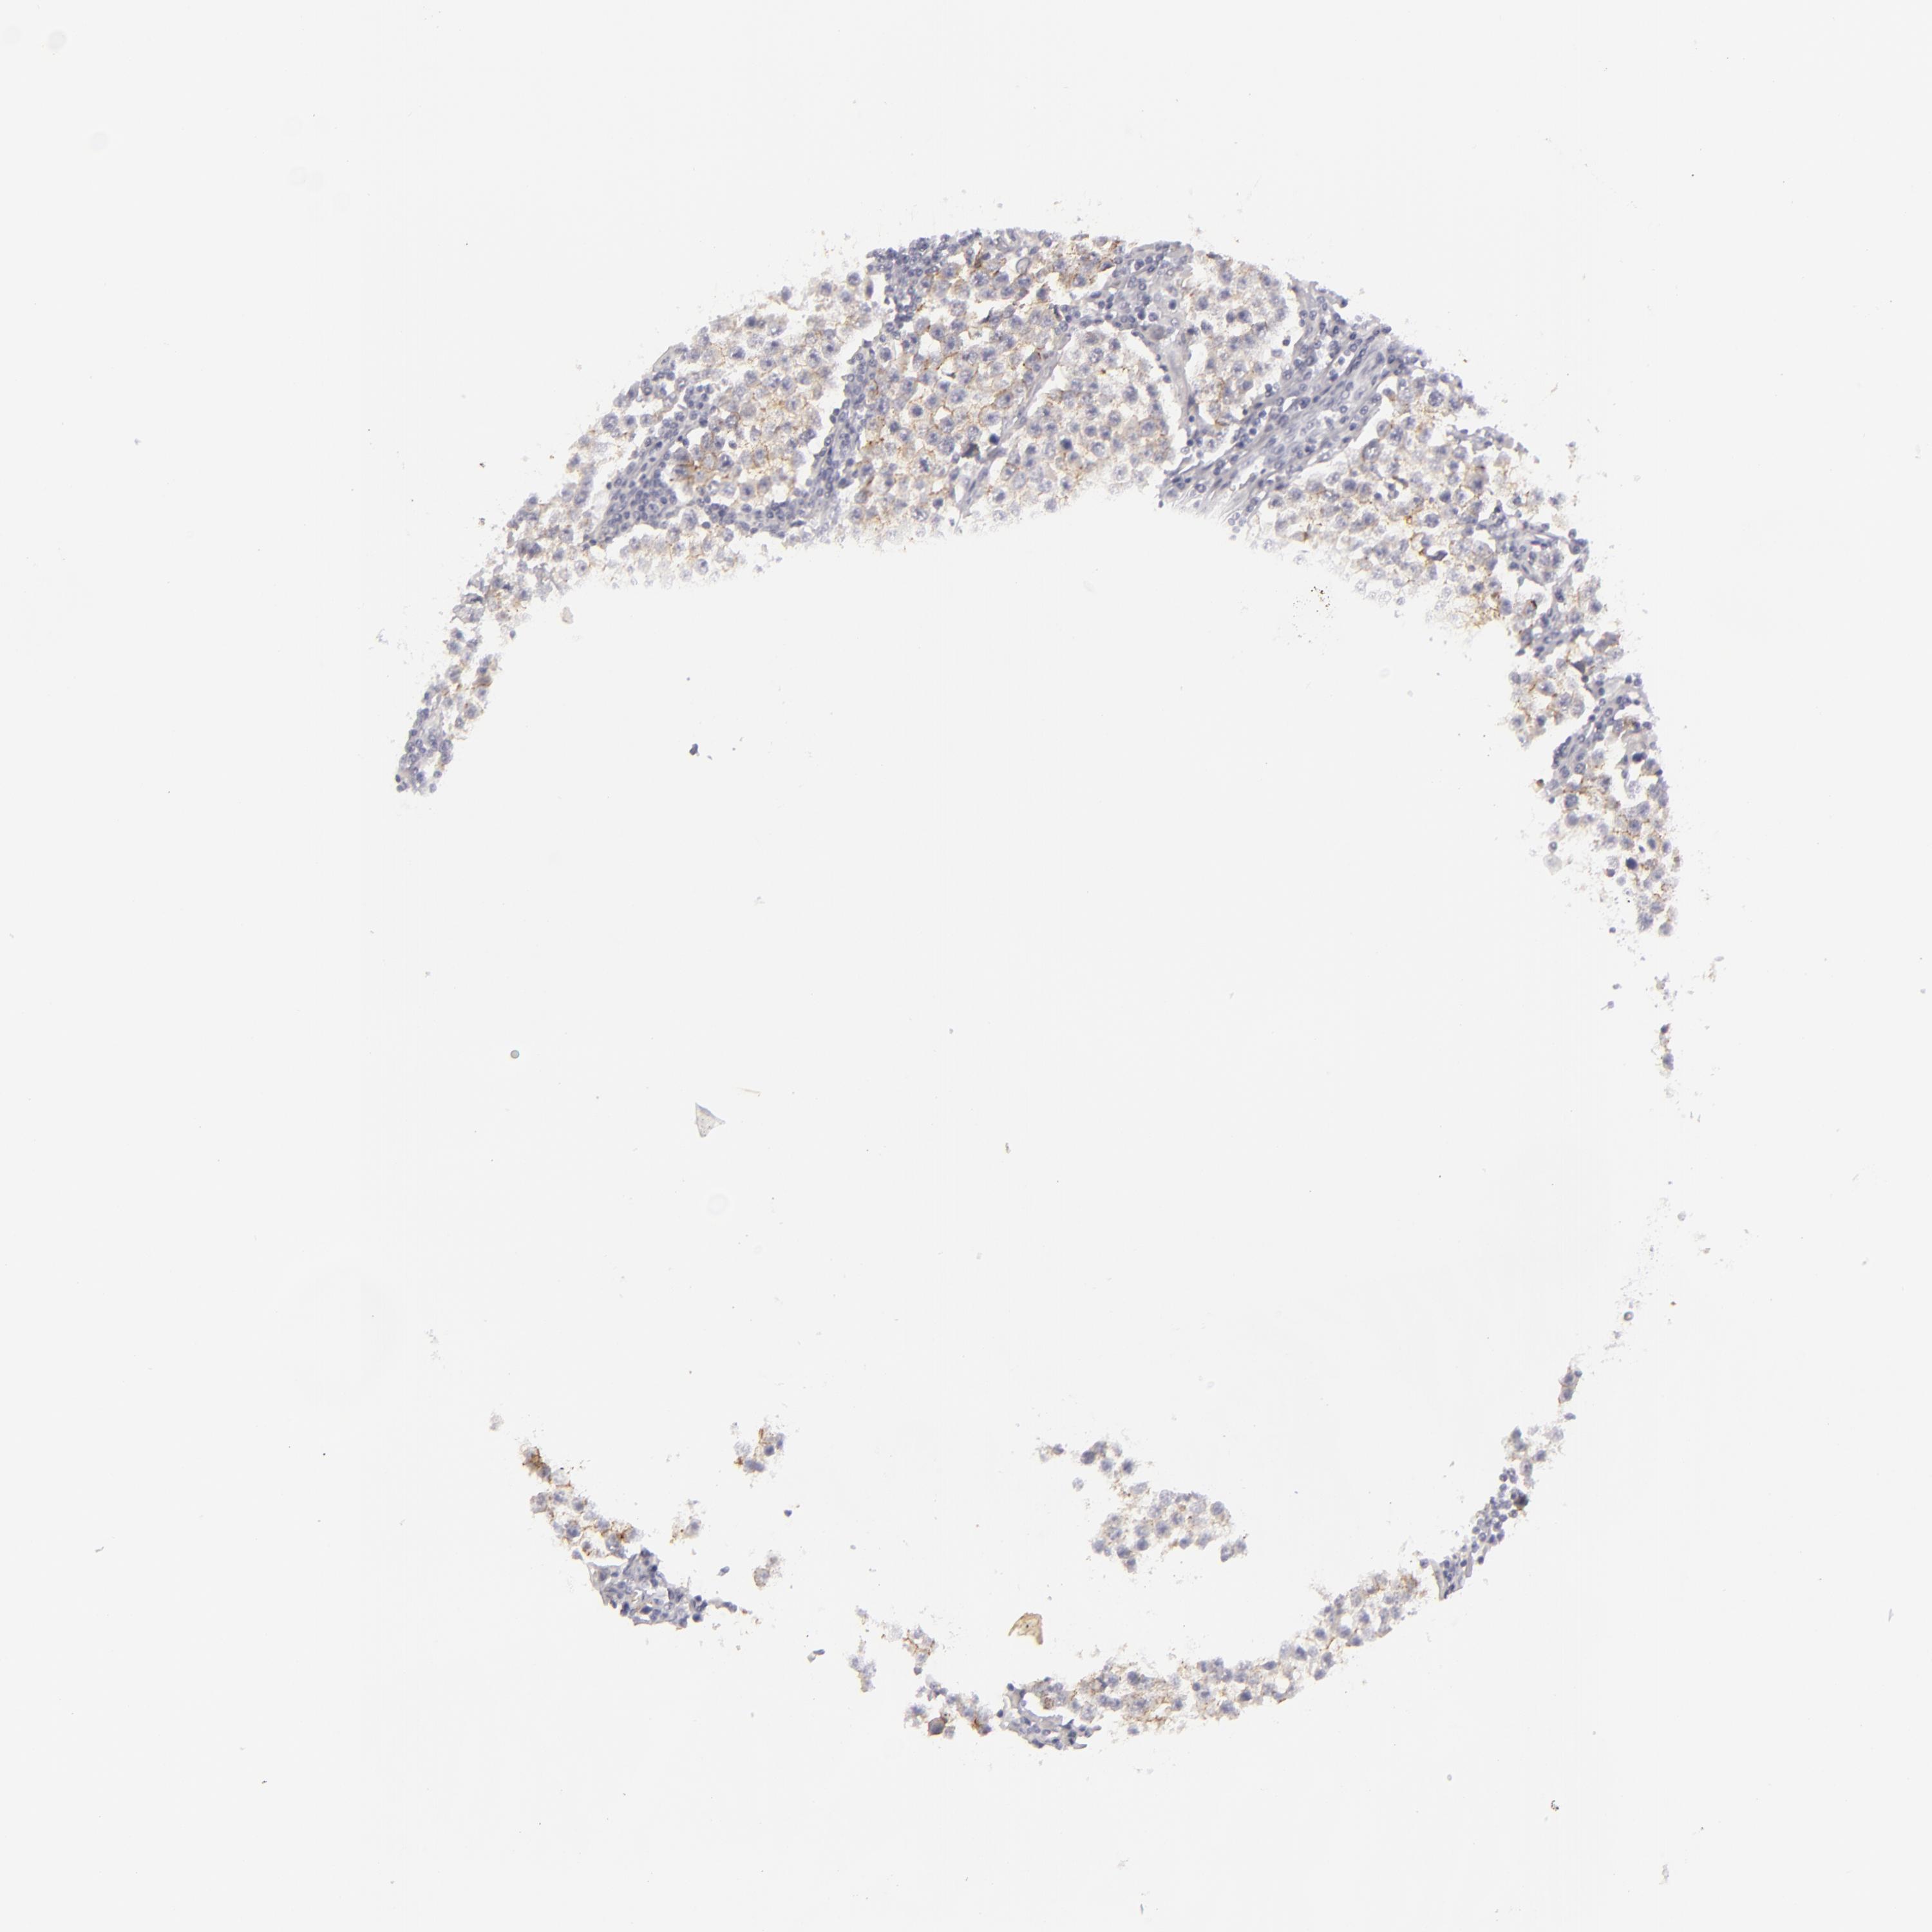

TESTIS CANCER - Protein expressioni

A mouse-over function shows sample information and annotation data. Click on an image to view it in a full screen mode. Samples can be filtered based on level of antibody staining by selecting one or several of the following categories: high, medium, low and not detected. The assay and annotation is described here.

Note that samples used for immunohistochemistry by the Human Protein Atlas do not correspond to samples in the TCGA dataset.

Antibody stainingi

Antibody staining in the annotated cell types in the current human tissue is reported as not detected, low, medium, or high, based on conventional immunohistochemistry profiling in selected tissues. This score is based on the combination of the staining intensity and fraction of stained cells.

Each image is clickable and will lead to virtual microscopy that enables deeper exploration of all samples and also displays staining intensity scores, fraction scores and subcellular localization as well as patient and tissue information for each sample.

Antibody CAB002139

Carcinoma, Embryonal, NOS

Seminoma, NOS